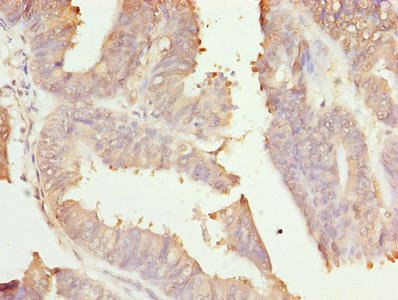

Immunohistochemistry of paraffin-embedded human gastric cancer using CSB-PA019567LA01HU at dilution of 1:100

Immunohistochemistry of paraffin-embedded human endometrial cancer using CSB-PA019567LA01HU at dilution of 1:100